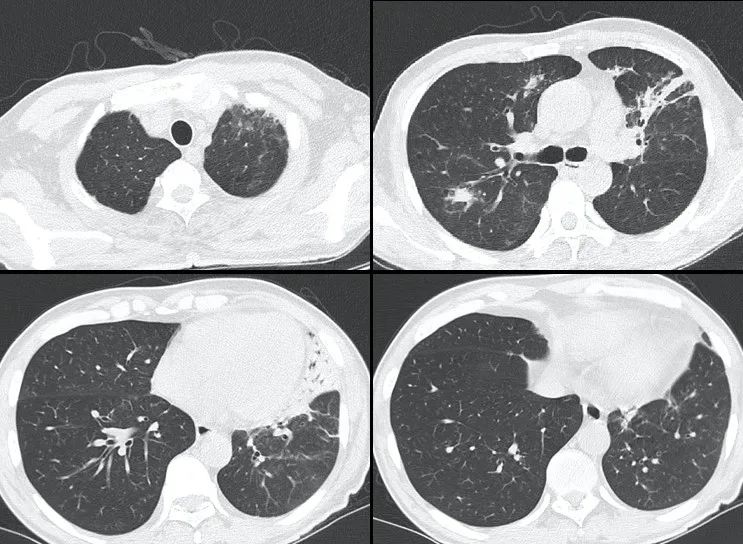

出院前复查CT明显吸收好转(如下)。